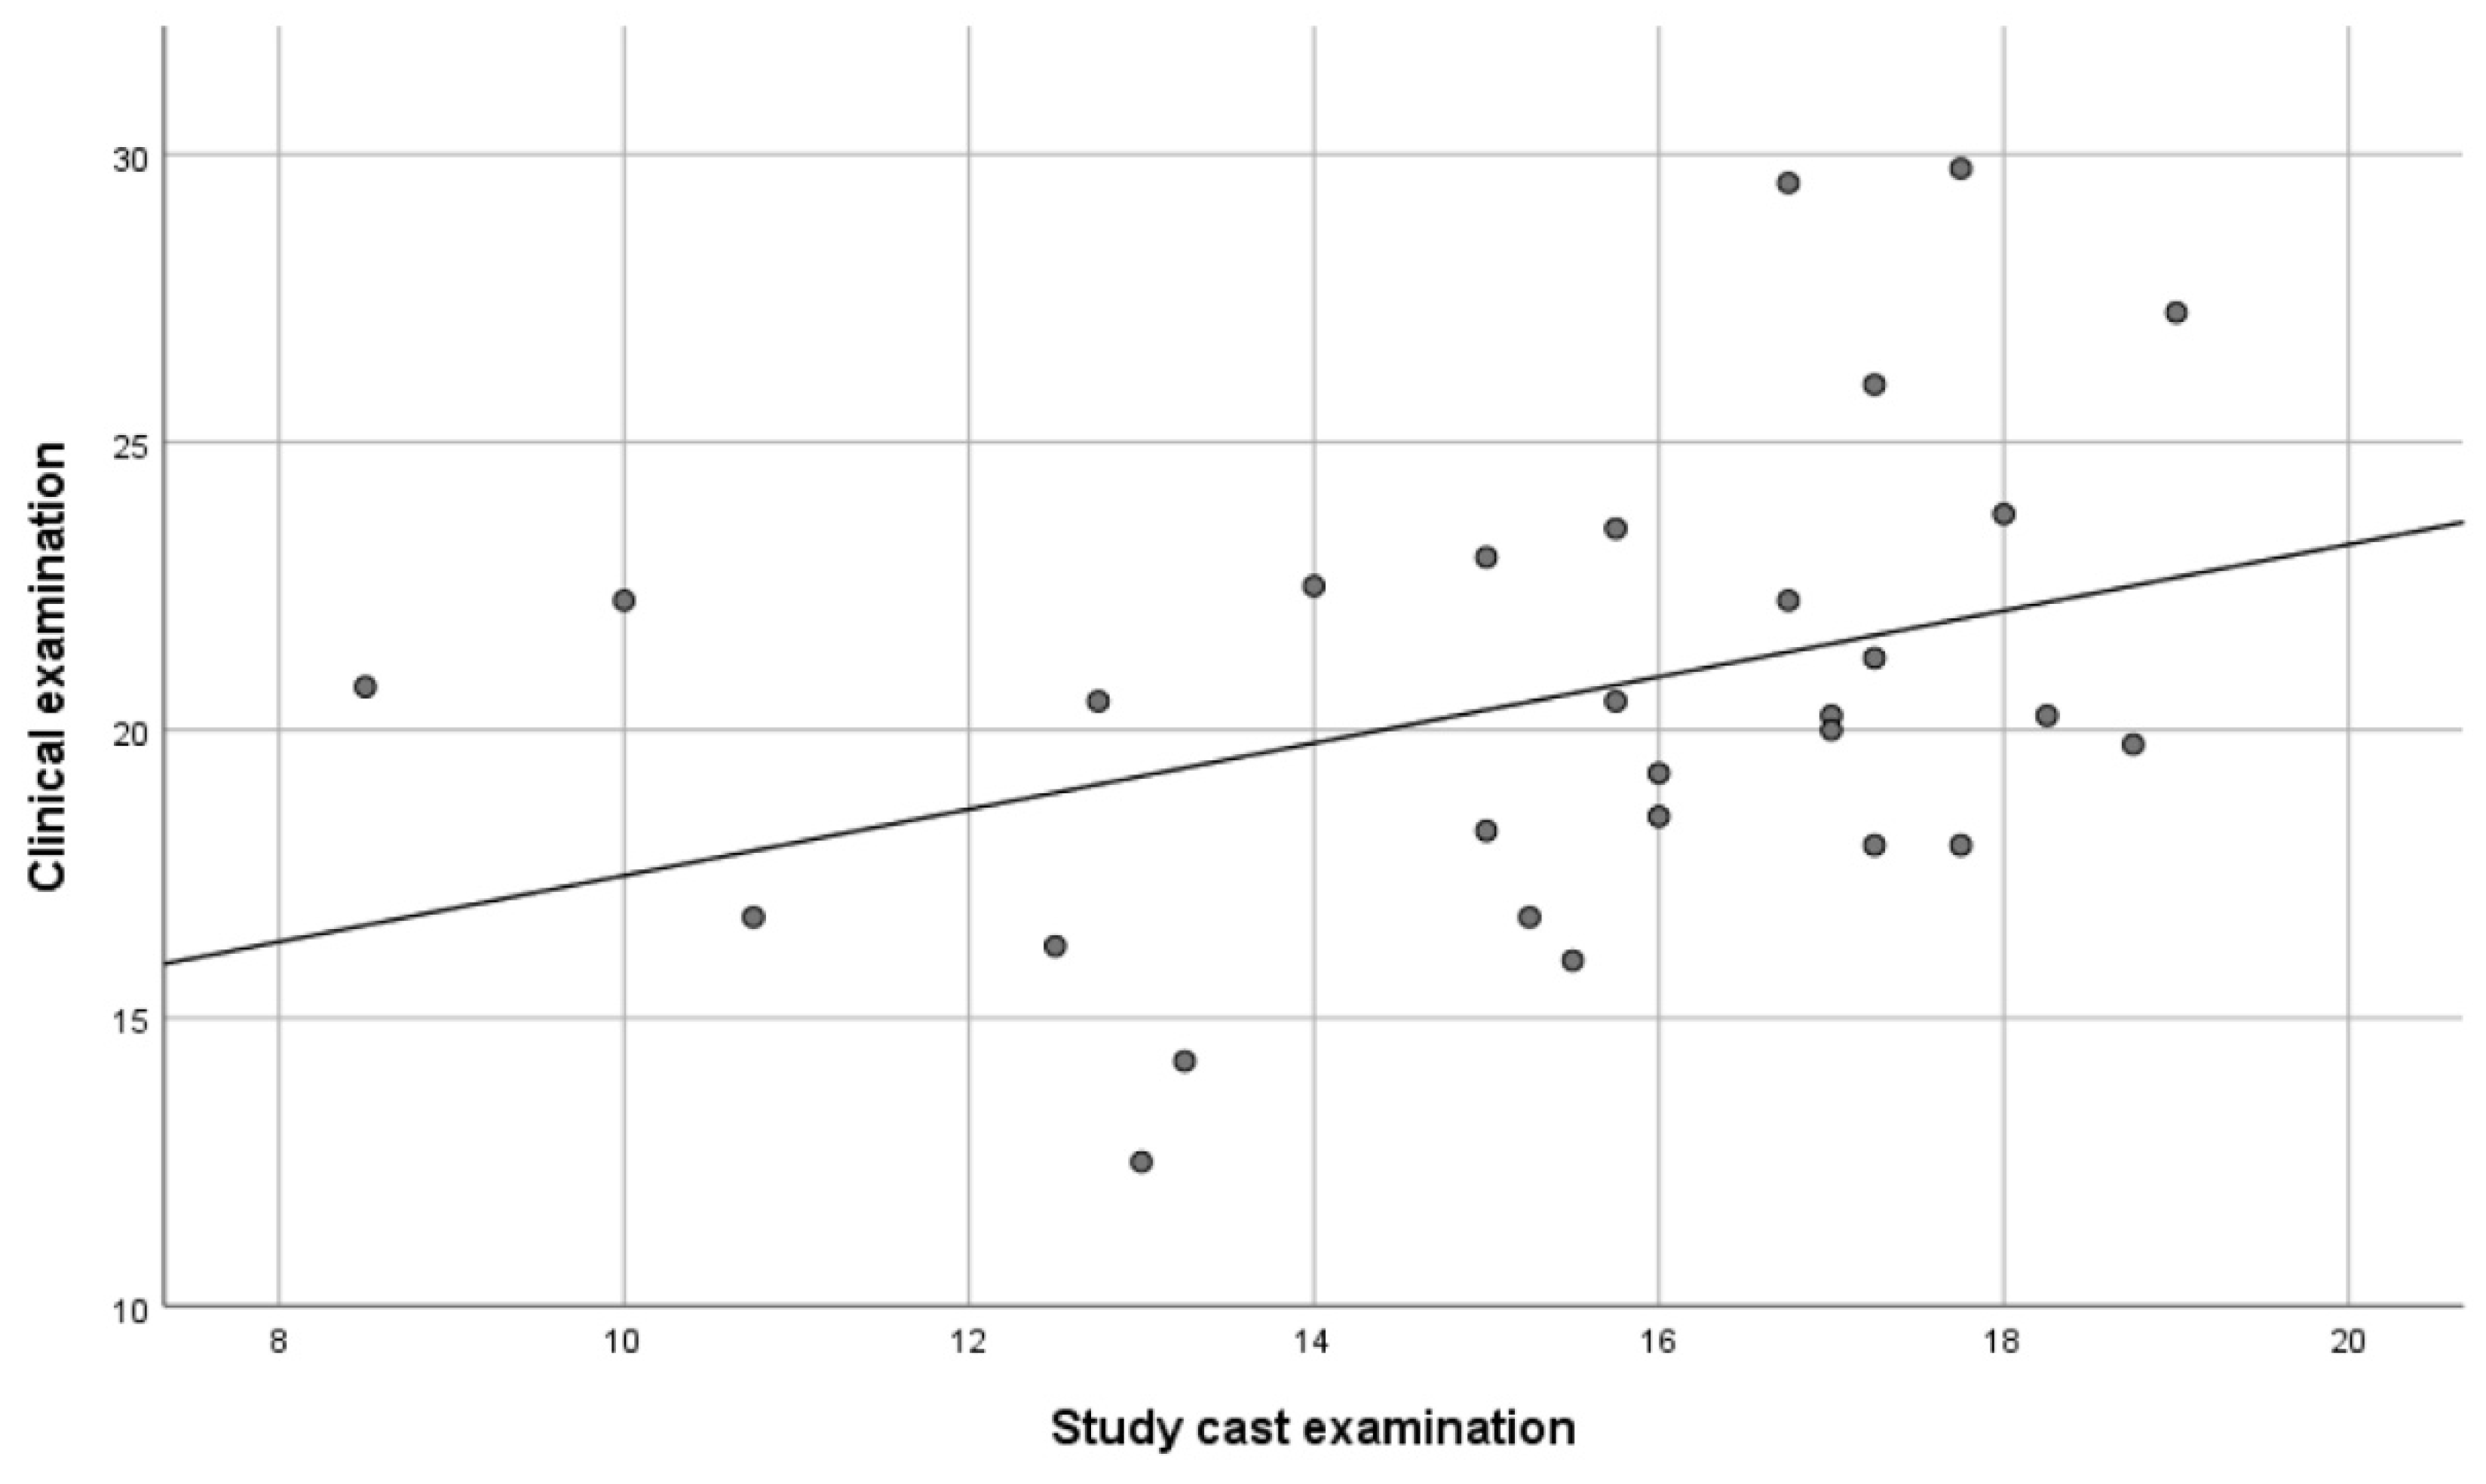

- a clinical examination with counting of the total number of occlusal contacts (CE method);

- a practical study cast examination with the measurement of the total number of occlusal contacts on stone casts mounted in an articulator (AE method);

3. Results